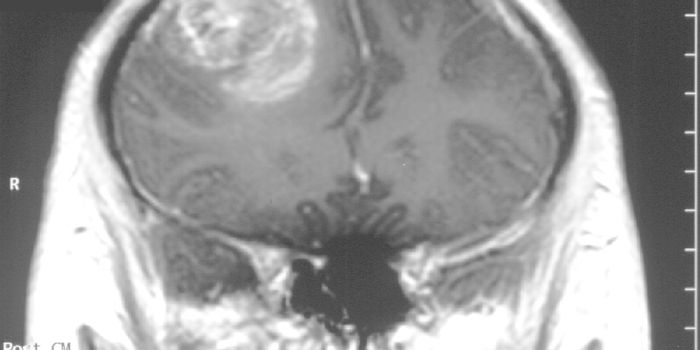

MAR 08, 2018ImmunologyOne of the most lethal forms of brain cancer owes most of its deadliness to its evasion of the immune system - a nasty t ...

APR 18, 2017ImmunologyA rare and lethal brain tumor more often than not leads to death not much longer than one year after diagnosis, even wit ...